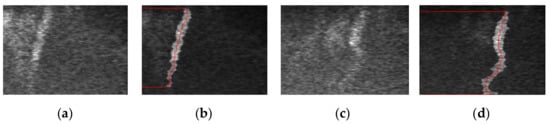

3.2. Shear Wave Velocity Estimation